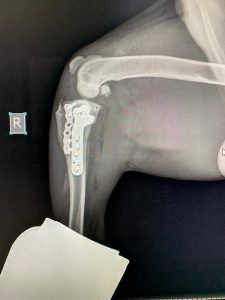

Hirurško liječenje rupture prednjeg križnog ligamenta koljena - TPLO

Za razliku od tradicionalnih metoda koje pokušavaju zamijeniti ili rekonstruisati ligament, TPLO mijenja biomehaniku koljena. Tokom zahvata, hirurg reže tibijalnu ploču (gornji dio goljenične kosti) i rotira je pod precizno izračunatim uglom kako bi se smanjio nagib zgloba. Time se eliminira klizanje femura po tibijalnoj ploči, koje nastaje zbog puknuća ligamenta, i stabilizira koljeno bez potrebe za ligamentom.